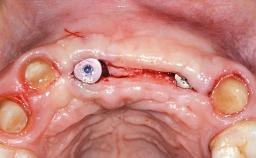

A 52-year-old male patient presented at our clinic, his concern being that most of his maxillary anterior dentition (teeth 13 to 22) was missing. This extensive tooth loss was due to trauma, which had occurred several years previously, after which the patient had been wearing a removable partial denture. He stated that the residual roots were asymptomatic, did not express any other concerns, and reported not having a routine dental history with regular dental examinations. His medical history was uneventful, and he did not smoke. A clinical and radiographic examination revealed the presence of generalized periodontal disease associated with fair to poor oral hygiene, moderate plaque, subgingival fracture of teeth 13 to 22 with a poor prognosis, defective restorations on several teeth (18, 17, 14, 24, 25, 27, 37, 45, 47, 48), periapical radiolucencies around several teeth (38, 35, 33, 43, 47), and erosive/abrasive lesions on most teeth (notably in the fifth sextant).